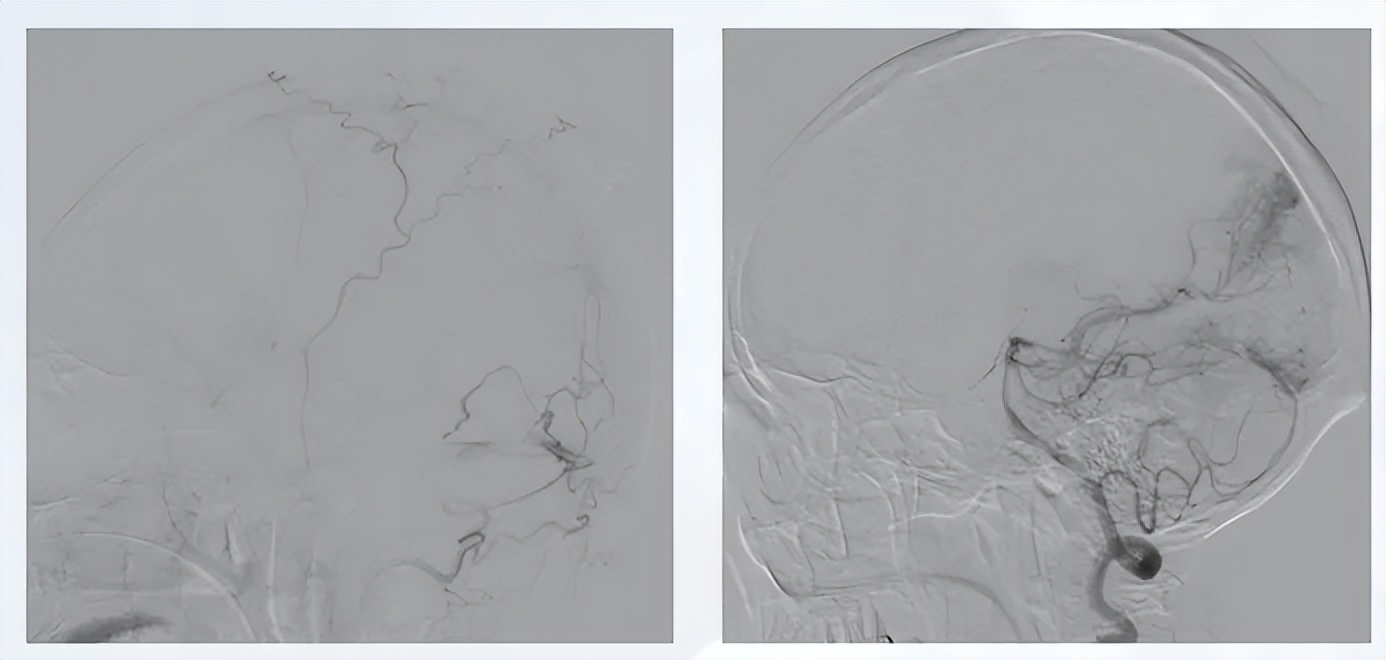

图3 脑动静脉栓塞-液态栓塞

图4 血管内治疗过程

治疗策略:采取“介入栓塞+神经内镜血肿清除+伽马刀放疗”的多阶段联合治疗。首先对大脑后动脉4支供血分支行介入栓塞,术中确保畸形团内安全栓塞,避免反流,栓塞后畸形团基本闭塞,仅深部少量可疑残留且流速流量极低;随后行神经内镜下单纯血肿清除,术后颅内情况稳定;术后两周造影复查见深部残留畸形显影,因残留病灶小于3 cm,予伽马刀放疗。